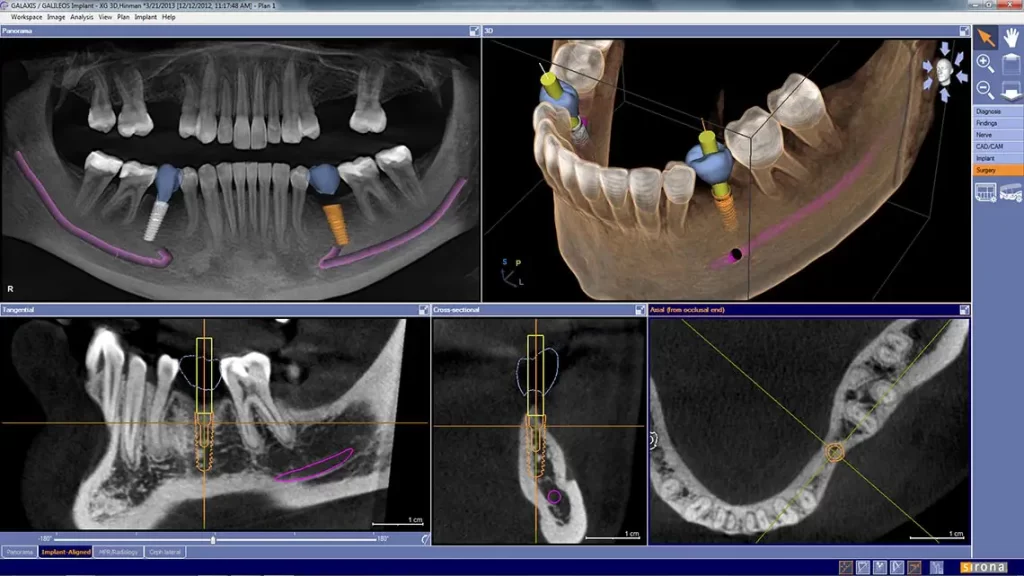

Calismiles is now offering advanced three-dimensional dental imaging to provide patients with the best treatment possible.

This dental imaging technology is particularly useful for dental implant treatment planning, root canal therapy, TMJ and other complex procedures, offering a quick scan that improves the opportunity to catch issues early.

This scanning process takes only 14 seconds and provides detailed images that increase clinical safety. The doctor will review the scan with the patient, using the rotating and moving image capabilities to enhance visibility.

By using this advanced technology, patients can easily see their teeth, upper and lower jaws, sinuses, and any issues that need immediate attention.

Overall, this 3D dental imaging system provides reliable and accurate results that ultimately improve patient care and satisfaction.